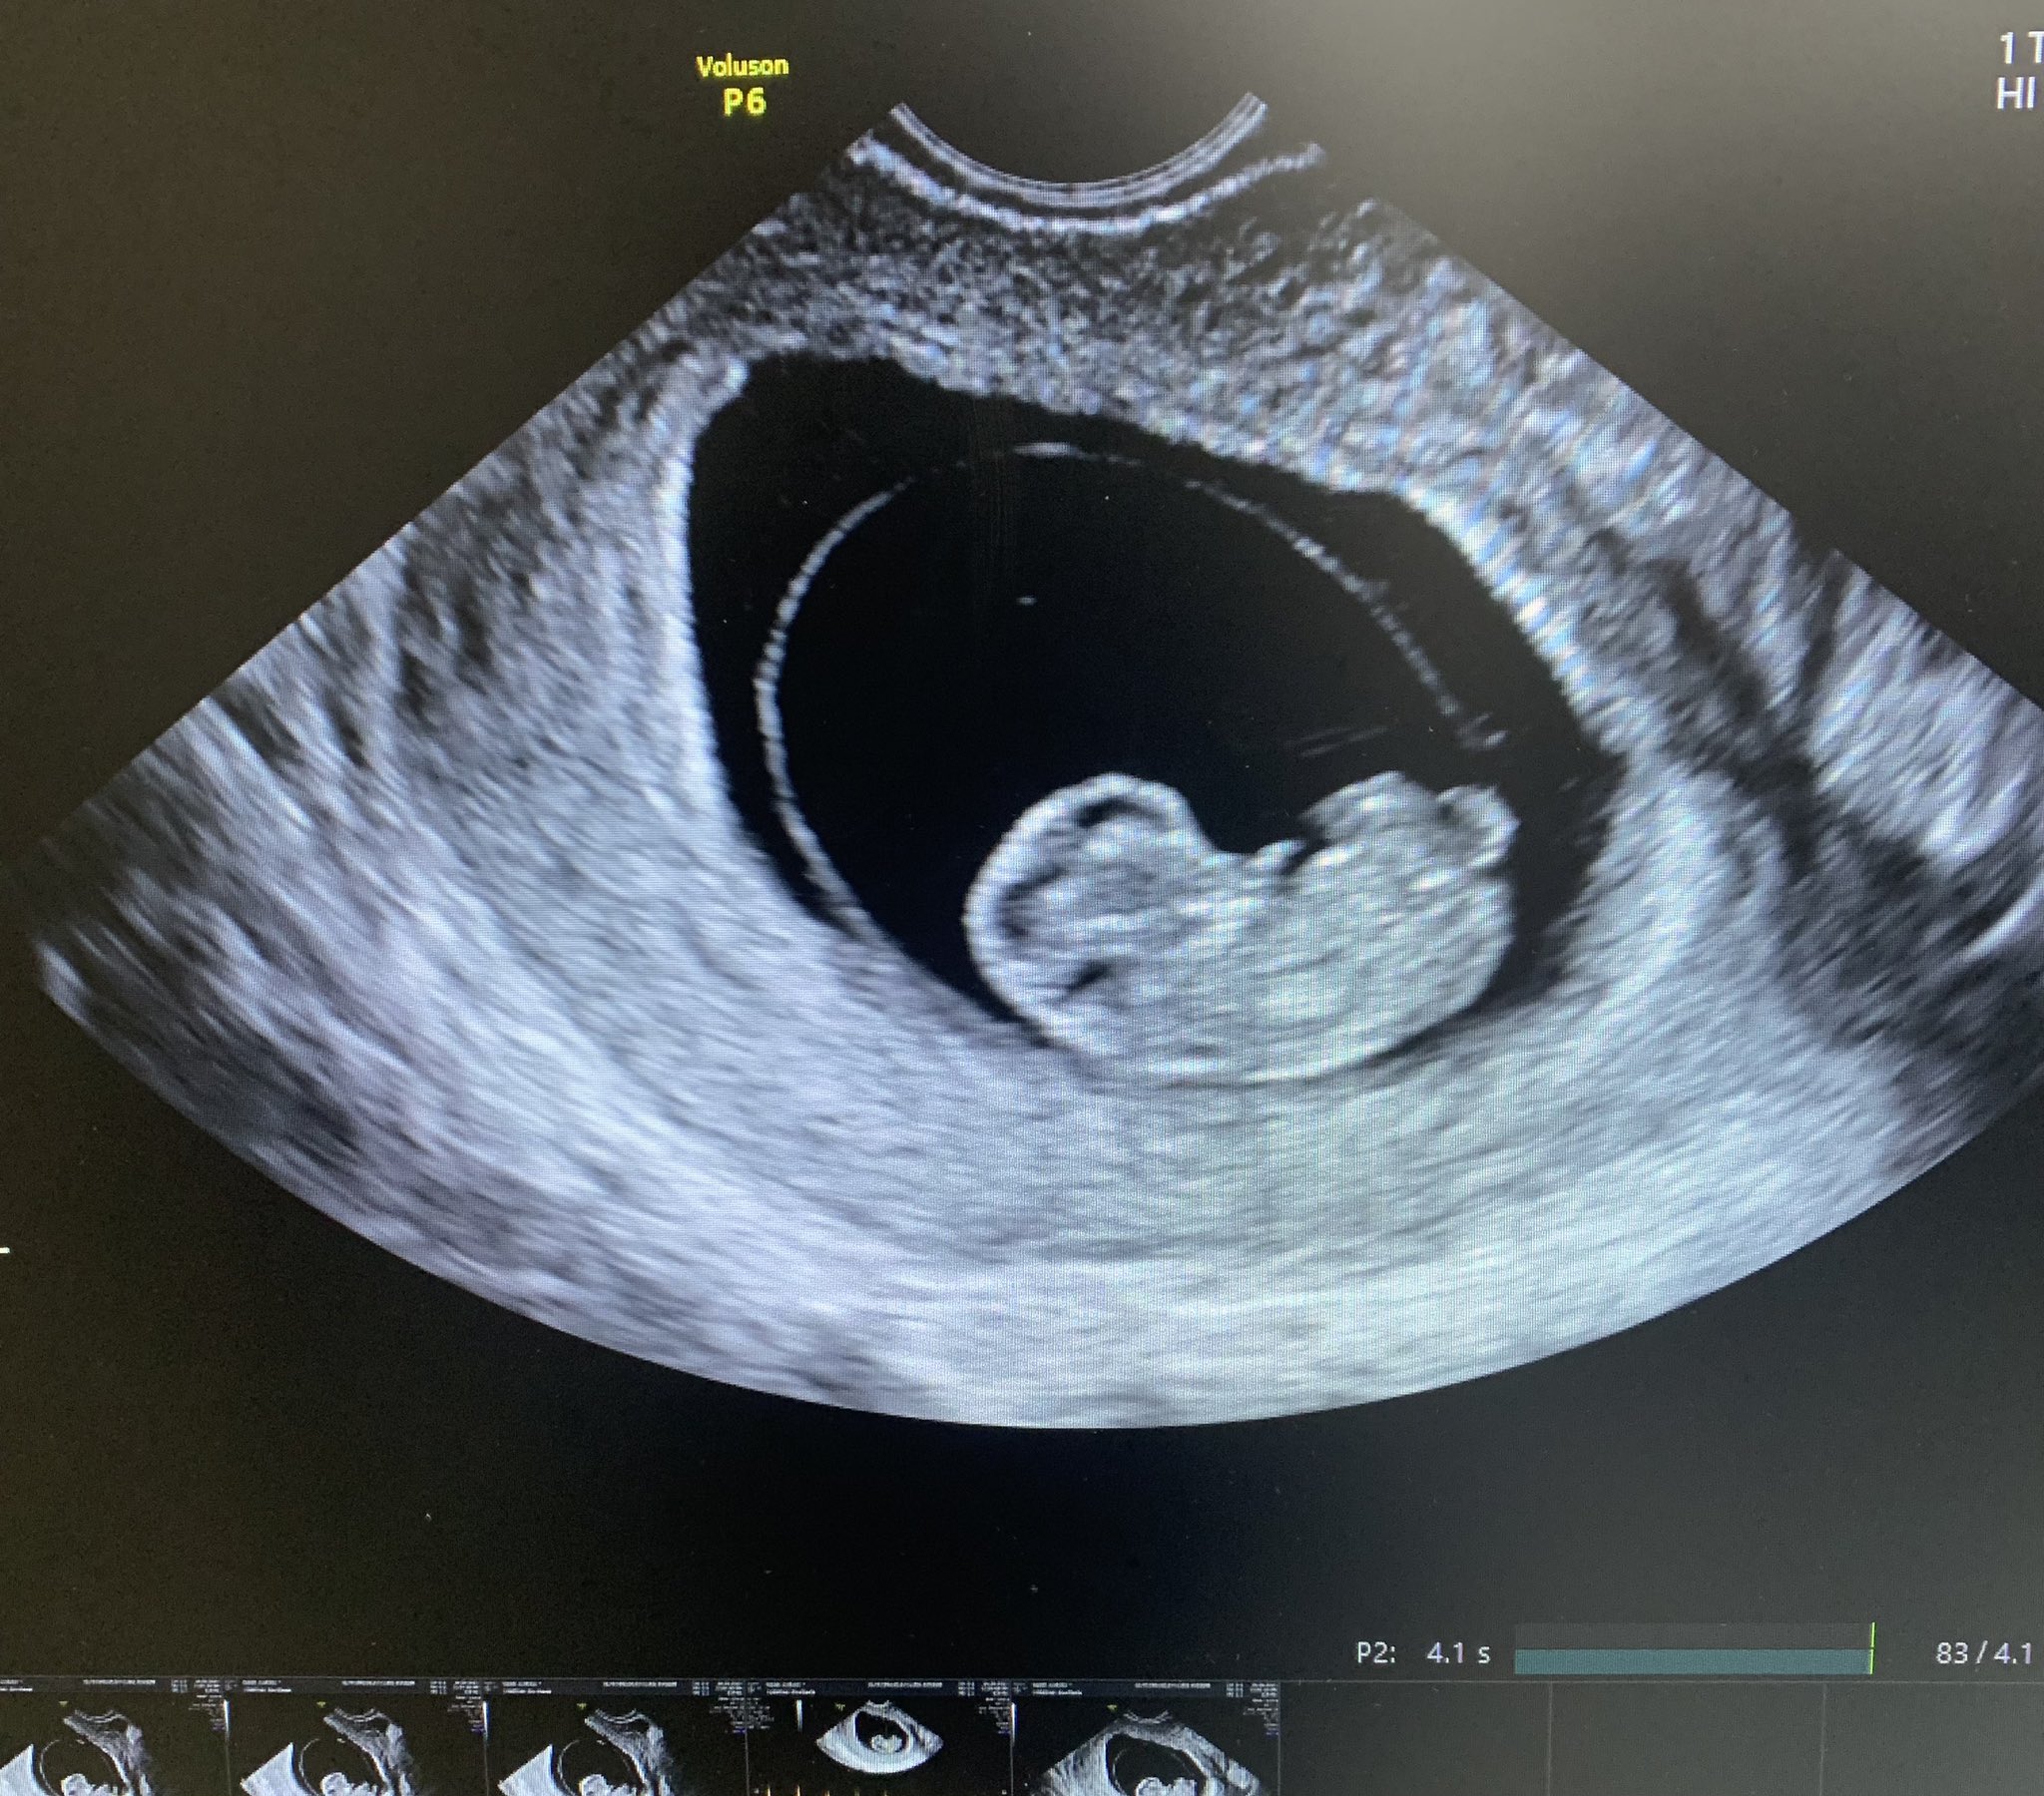

عندما ترى "الصوت"

صورة الجنين باستخدام الموجات فوق الصوتية من أهم التقنيات التي غيرت طب وجراحة النساء والولادة. صورة تدخل السعادة على من ينتظرها سنوات.